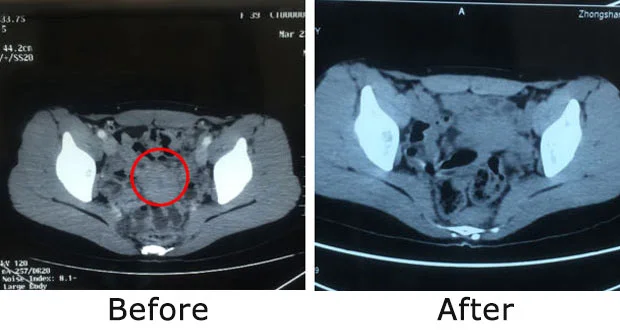

Ovarian Cancer Case

Winda

Nationality: Indonesian

Diagnosis: Ovarian cancer stage IV (postoperative recurrence with mediastinal and supraclavicular lymph node metastases)

Treatment Process: Winda underwent surgery for ovarian cancer in 2016, but relapsed a few months later and was diagnosed with stage IV cancer. Upon arrival, she was extremely weak. The MDT designed an interventional therapy + natural therapy plan, preserving her uterus and ovaries. After three sessions, the pelvic lymph node tumors completely disappeared. Following medical advice, she adopted a healthy lifestyle and later gave birth to a healthy baby.